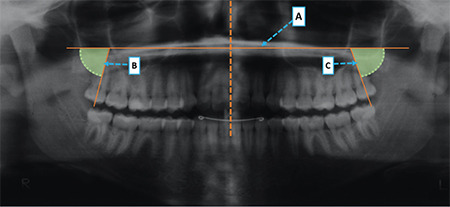

Methods: The sample comprised 93 patients divided into four groups: Group 1, Class I malocclusion treated with first premolar extractions; Group 2, Class I malocclusion treated without extractions; Group 3, Class II malocclusion treated with first premolar extractions; and Group 4, Class II malocclusion treated without extractions. Panoramic radiographs were used to evaluate the third molar mesiodistal angulations at T1 (pretreatment), T2 (posttreatment), and T3 (long-term posttreatment). Third molar eruption status was assessed in dental casts. Intergroup angulations and eruption status comparisons were performed using one-way analysis of variance (ANOVA), followed by Tukey's test and Kruskal-Wallis test, respectively.